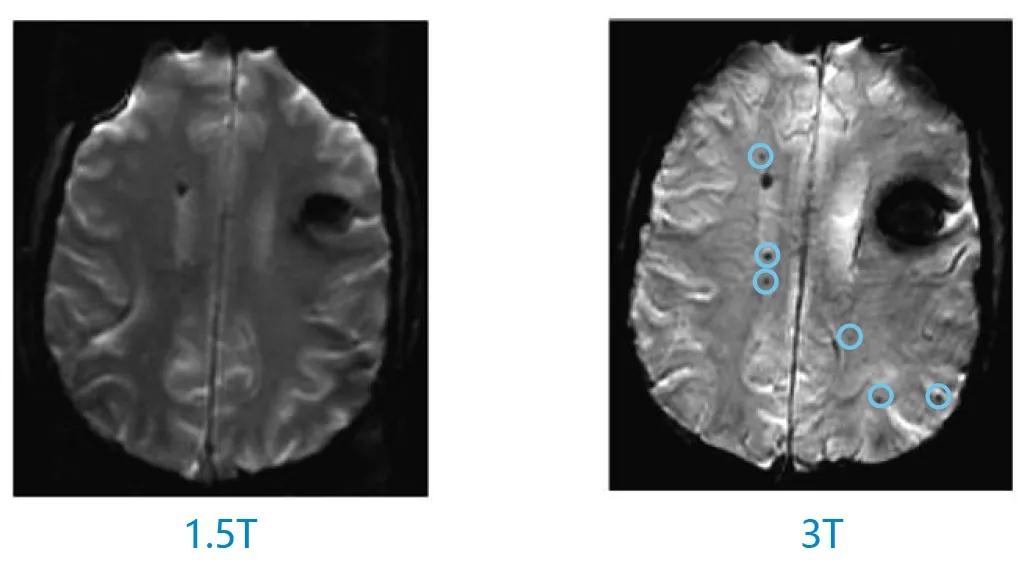

磁共振系统有1.5T和3T等不同场强。其中“T”代表特斯拉。特斯拉被定义为用于描述MRI中使用的磁体强度的测量单位。磁体是MRI(磁共振成像)中的M,该磁体是获取MRI图像的基础。磁体的强度直接影响这些图像的质量。随着MRI技术的发展和进步,与1.5T相比,3T具有扫描速度快、图像质量更清晰的特点,能够给患者带来更多临床益处,并能够在更多科研场景下进行应用。随着大型三甲医院3T MRI装机越来越多,患者也拥有了享有更优质医疗资源的机会。因此,对于3T MRI兼容起搏系统的需求也随着增长,在这一背景下,美敦力研发团队通过两百万以上测试模型验证,攻克难关,率先推出3T MRI全身兼容系统。在获得中国国家药品监督管理局(NMPA)批准前,该系列产品已经得到了欧洲CE和美国FDA认证。

1.5T上无法察觉的病灶在3T上清晰可见2

2.Alvarez-Linera J. Eur J Radiol. 2008;67:415-426.